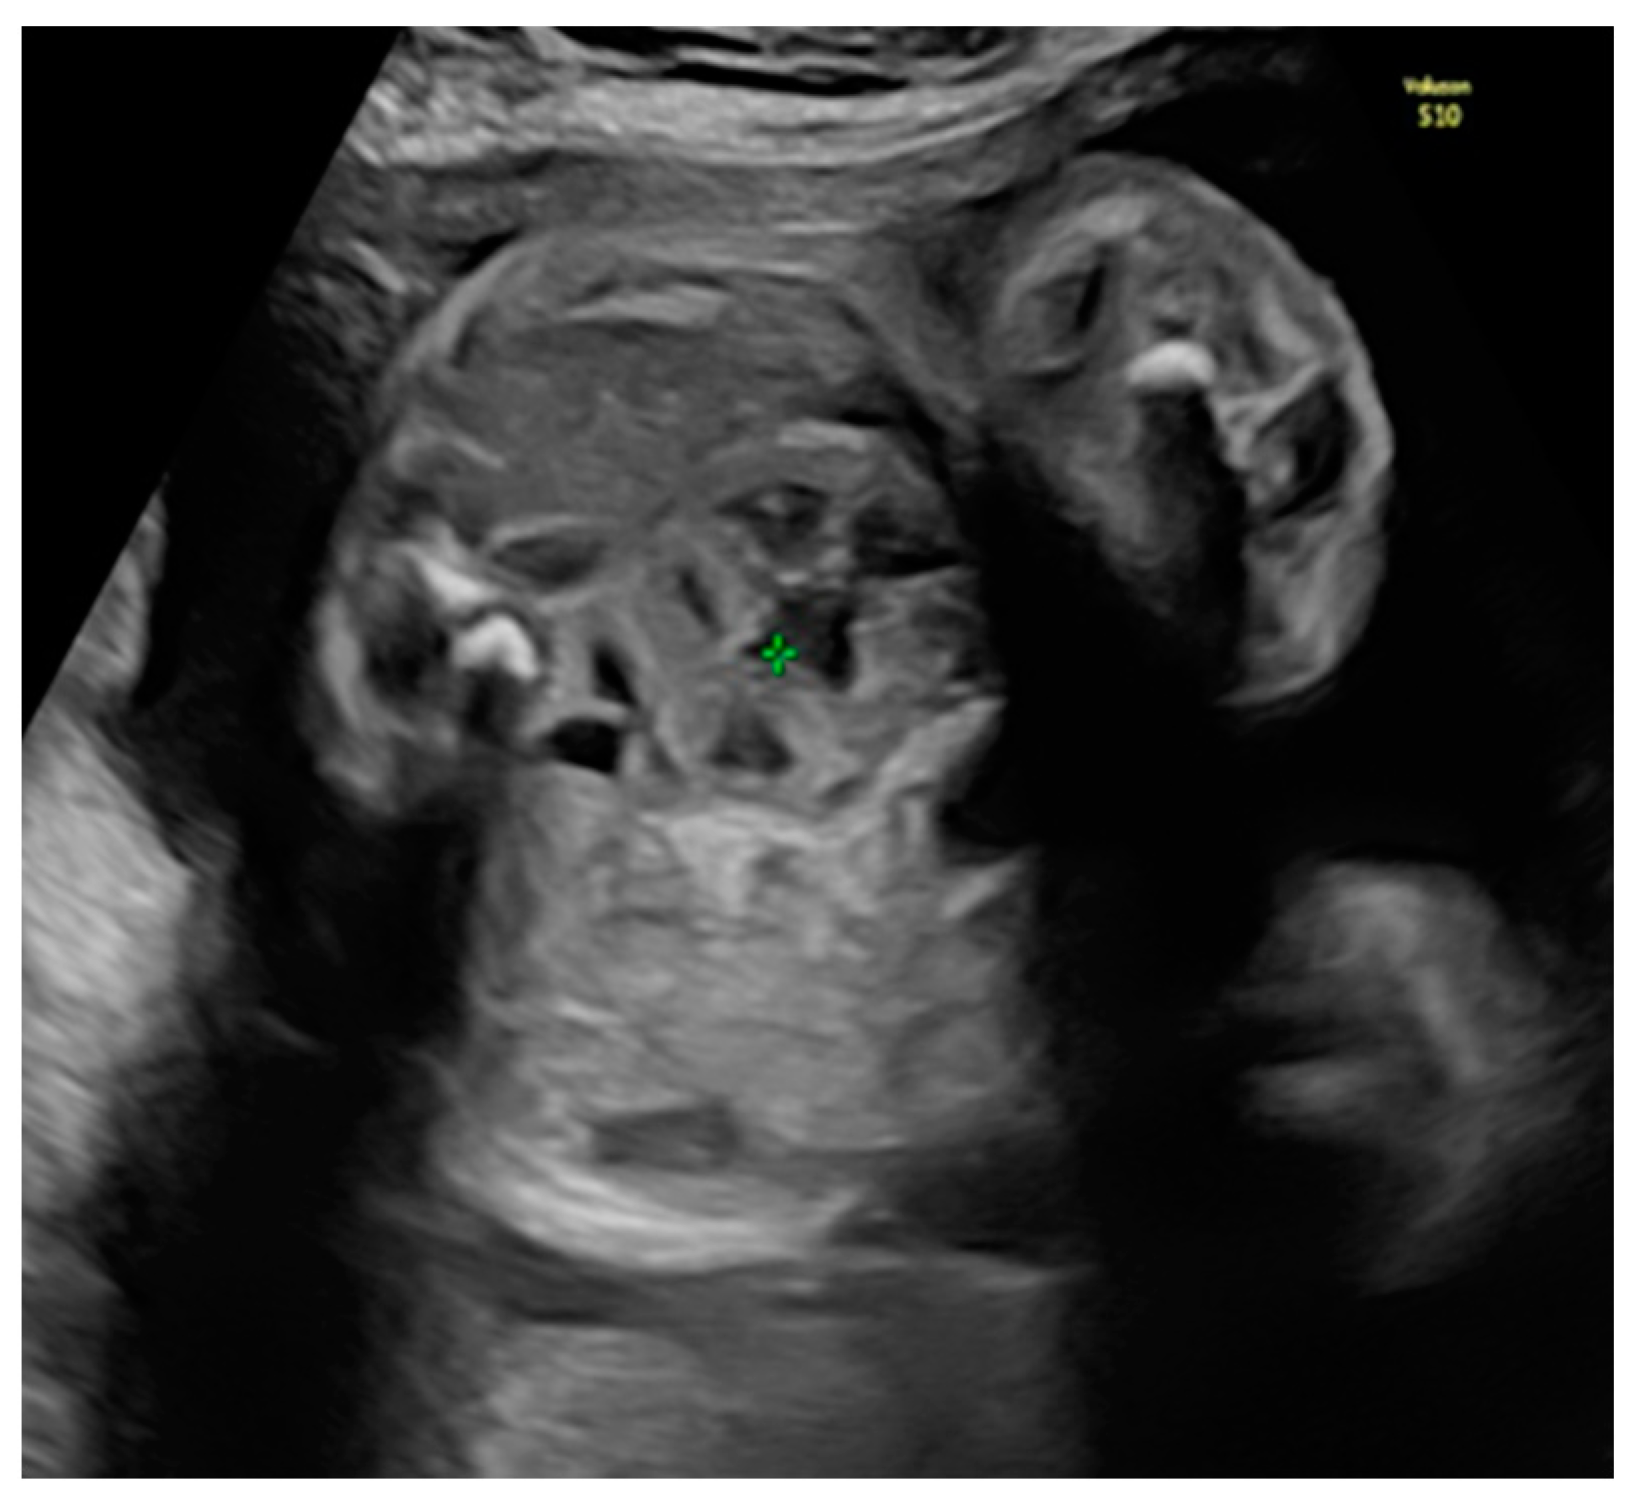

She returned at 20 weeks and 4 days for the second-trimester anomaly scan. Our careful ultrasound examination revealed bilateral empty renal fossa, a normal bladder, and normal amniotic fluid volume. No other fetal anomalies were detected, and the fetus was normally grown. Renal tissue was found in the fetal pelvis, close to the bladder and to the right (Figure 1). On a transvaginal scan, we demonstrated a duplex kidney with two renal pelvises (Figure 2a,b). The artery supply was seen coming from the internal iliac artery (Figure 3a,b). We offered invasive testing, but the patient declined. A fetal echocardiography was also performed, which showed no abnormalities of the fetal heart.

Figure 2. Transvaginal scan assessment: (a) Visualization of the right duplex kidney. (b) Sagittal view of the right duplex kidney.